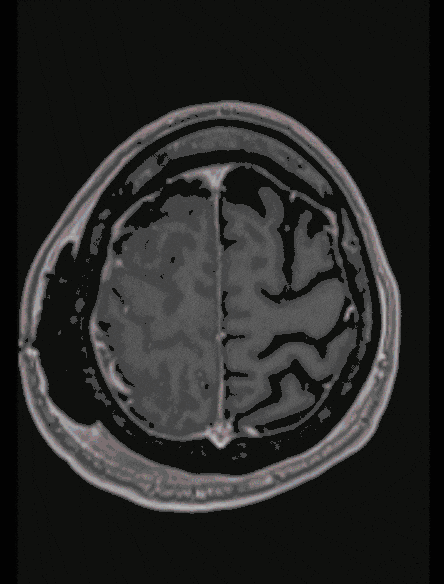

Oligodendroglioma

Oligodendrogliomas, similar to other gliomas, are usually benign tumors with slow growth. However, they can change and become malignant even after years. Therefore, complete microsurgical removal is usually considered.